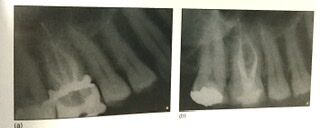

右側が学生時代の教科書にある削り方。

でも左側は極端に小さくて、忍者みたいと表現されてます。

左側は凄いんですが、流石に取り残しや見逃しが多くなり、この中間がお勧めされます。